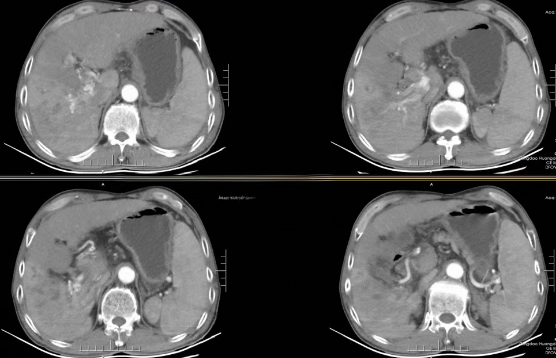

术前增强CT示肝右叶肿块伴门脉瘤栓形成

术中造影、栓塞、注射化疗药物

术后复查CT,可见瘤体内碘油沉积良好